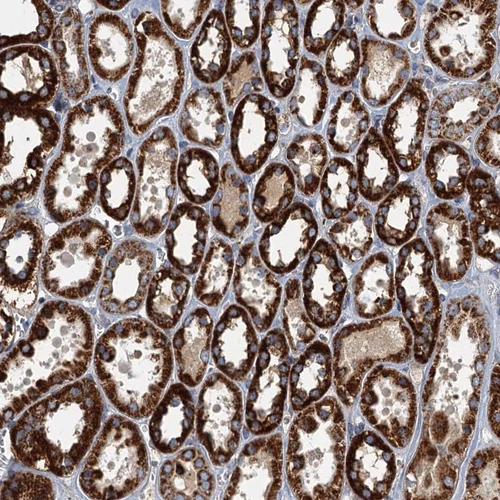

Immunohistochemical staining of human kidney shows strong cytoplasmic positivity in tubular cells.